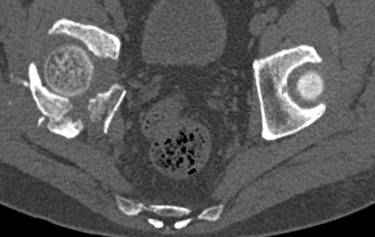

Re: перелом правой половины таза

высылаю дополнительно сканы.